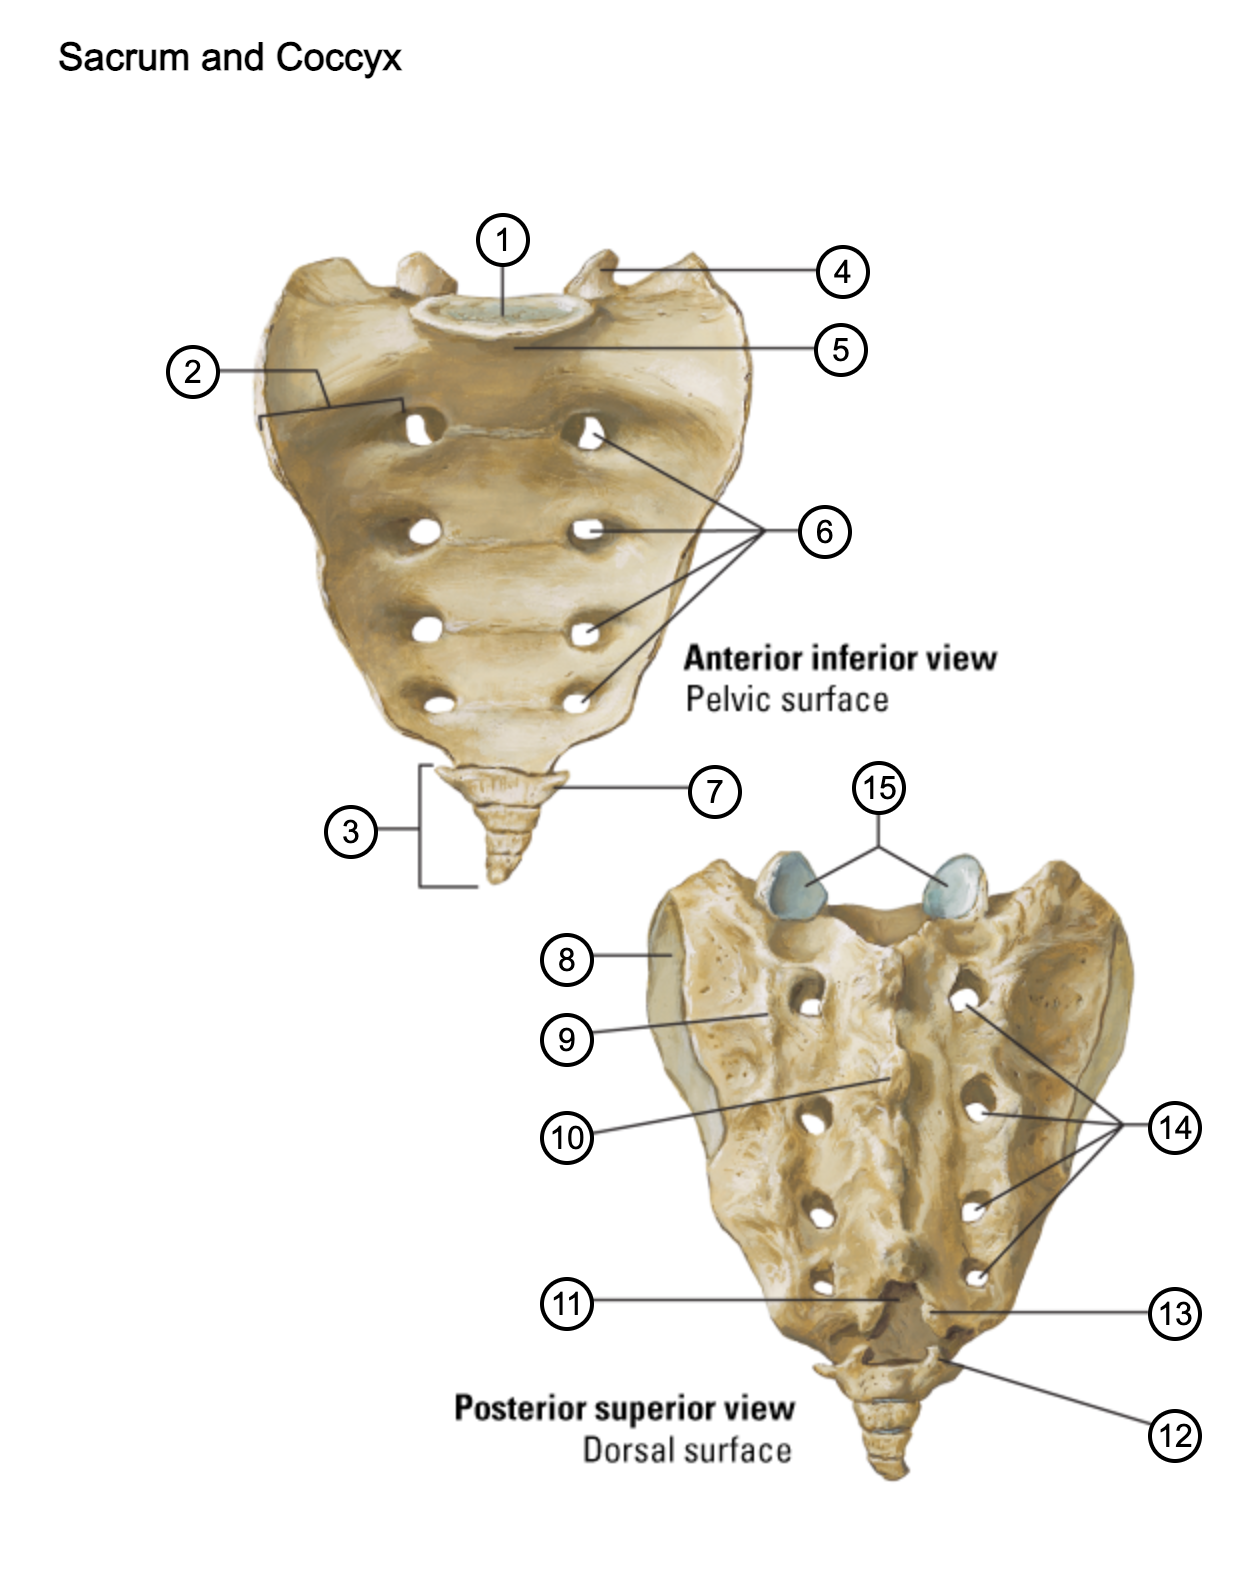

1

lumbosacral articular surface

2

ala of sacrum

3

coccyx

4

superior articular process

5

promontory

6

anterior sacral foramina

7

transverse process of coccyx

8

auricular surface

9

lateral sacral crest

10

median sacral crest

11

sacral hiatus

12

coccygeal horn

13

sacral horn

14

posterior sacral foramina

15

facets of superior articular processes